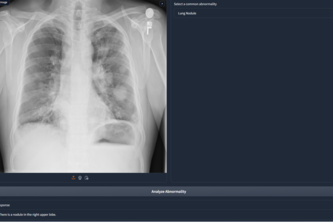

Get an assessment on various Chest X-Rays by 🧠AI